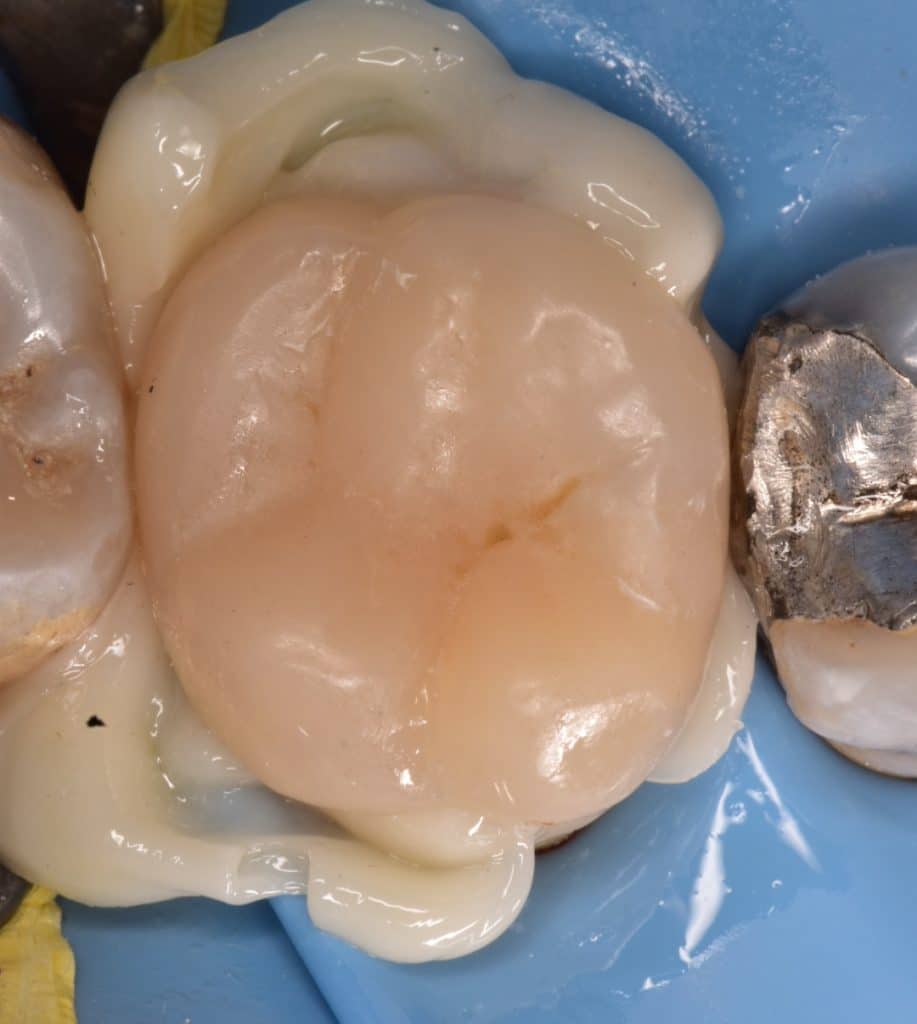

Cementation day

Isolation, the biobase treatment was : sandblast _acid etching-bond without curing

Cementation with heated composite